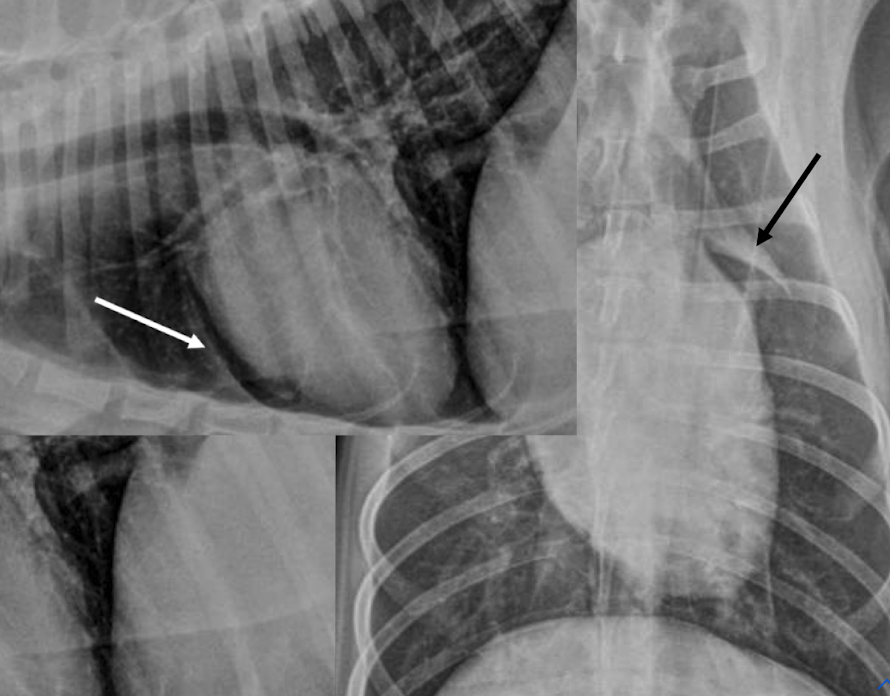

what is this showing

left: enlargment of middle tracheobronchial Lymph node → ventral displacement of carina

right: left atrial enlargmentdorsal displacement of carina

both will show bowing of the mainstem bronchi on VD (cowboy) and double opacity sign